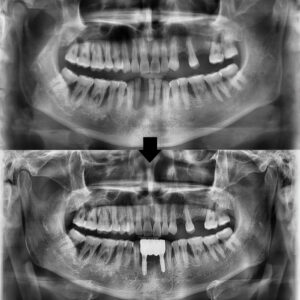

25.08.22

자세하게 확인하기 위해

파노라마를 촬영해보았습니다.

파노라마 상에서 기존 보철물 하방으로

충치가 진행된 양상이 확인되었고,

일부 치아에서는 치근 파절이

의심되는 소견도 함께 관찰되었습니다.

이로 인해 단순한 보철 교체만으로는

예후가 좋지 않을 것으로 판단되었습니다.

그래서 병점치과 365서울차오름에서는

앞니 브릿지 전체 제거 후

충치가 깊고 파절 및 인공치 부위는

임플란트를 진행하기로 하였습니다.

또한 비교적 상태가 유지된 잔존 치아들은

필요 시 신경치료를 시행한 후

크라운으로 마무리하여

기능과 심미성을 함께

회복하기로 하였습니다.

25.08.22 / 26.01.16

치료 전후 사진입니다.